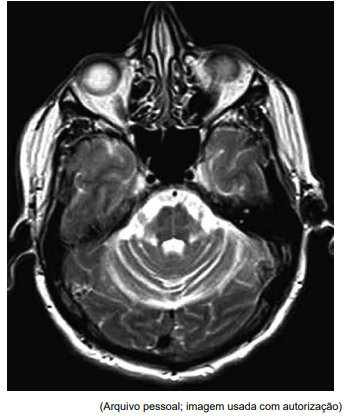

Homem de 56 anos apresenta quadro de tremor de repouso bilateral nos membros superiores há seis meses. Ao exame físico, apresentava tremor de repouso bilateral de frequência moderada, ligeiramente mais acentuado no membro superior direito do que no esquerdo, e rigidez em roda dentada bilateral, que parecia ser igual em ambos os membros; bradicinesia significativa que afeta ambos os lados do corpo. Foi-lhe prescrita levodopa, que teve pouco efeito sobre os sintomas. No acompanhamento, um ano depois, ele relata instabilidade significativa na marcha. Nesse momento, o exame mostra dismetria bilateral, e sua marcha é ampla e ligeiramente cambaleante. Uma ressonância magnética (imagem axial ponderada em T2) é realizada e mostrada a seguir:

Enunciado 4918966-1

Qual é o diagnóstico mais provável para esse paciente?